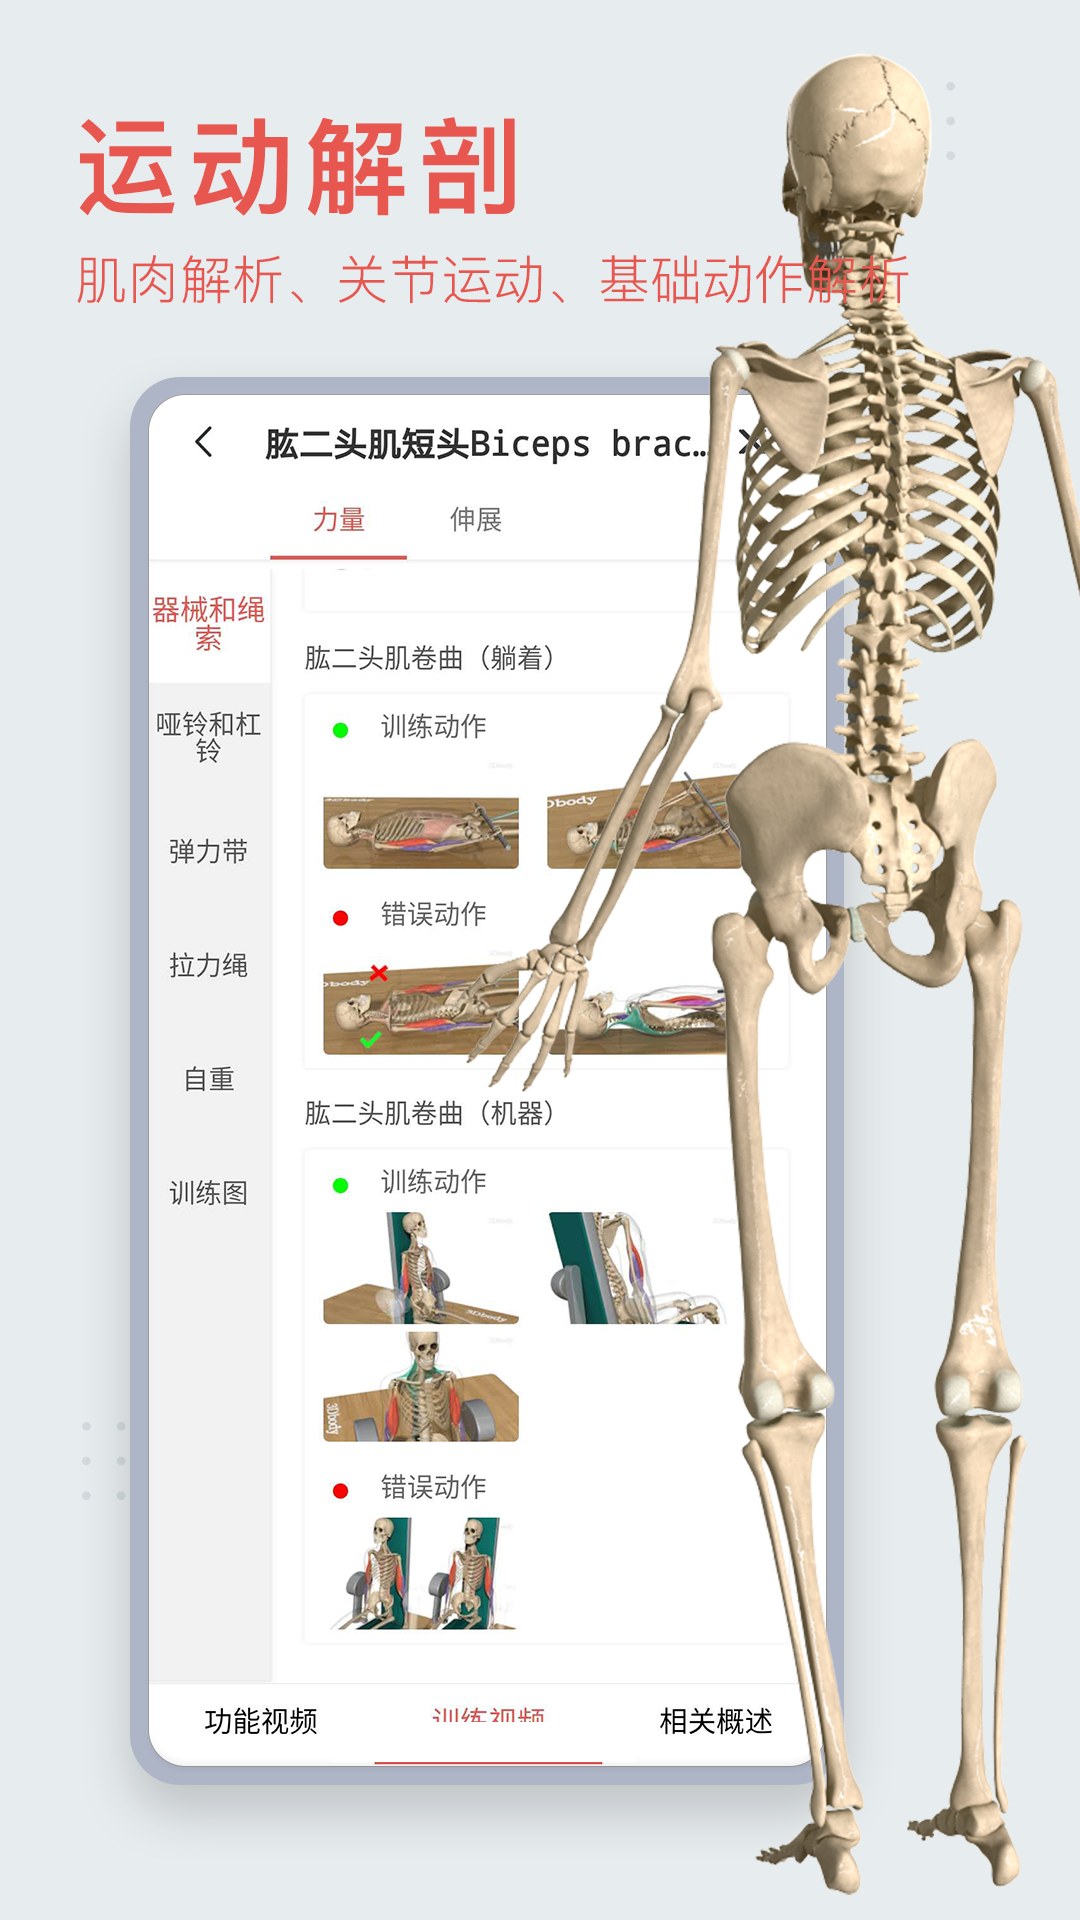

3dbody系统解剖手机版是专为医学行业打造的掌上人体解剖学习软件,详细的三维解刨图片,解释详尽。3DBody系统解剖手机版是系统模块,相较于局部模块版,解剖更加的详细,需要的赶紧下载吧。

3DBody作为集大成者,不仅数据详实,而且操作功能强大,国内外高度领先,通过本软件实时三维操作,轻易获得层层解剖人体的机会。作为内容最全面的3D解剖app,电脑版本已经被证实为最受欢迎的医学软件之一。

软件包括人体十二大系统的3D解剖.经络穴位和反射区,同时提供大量肌骨康复动画,全部三维体验,界面精美,内容专业,操作体验佳。

*运动功能解剖